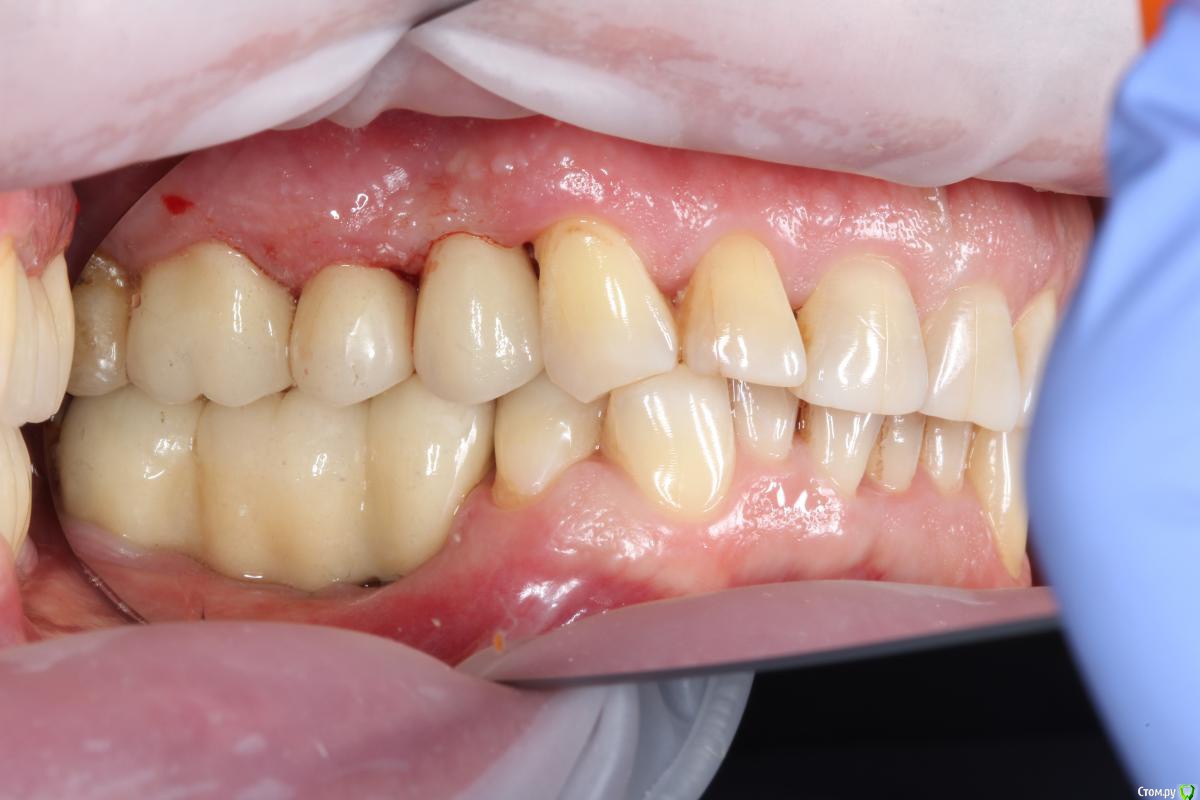

anvladd Опубликовано 20 марта, 2018 Автор Поделиться Опубликовано 20 марта, 2018 Вот так во рту Ссылка на комментарий

makinos Опубликовано 20 марта, 2018 Поделиться Опубликовано 20 марта, 2018 Если работу недавно сдали, значит модель в клинике еще. Откручивайте и в лабу, пусть все расклеивают). Добавят керамики, которую вы спилили и вклеют по-людски. Там на 35 тоже не все гладко, по-моему. Так оставлять- не вариант. 3 Ссылка на комментарий

BadMojo Опубликовано 21 марта, 2018 Поделиться Опубликовано 21 марта, 2018 У меня первая мысль - контактный пункт м\у коронкой на импланте и 38 слишком плотный и не дает досадить мост. Ссылка на комментарий

Паращук Роман Опубликовано 21 марта, 2018 Поделиться Опубликовано 21 марта, 2018 Пустили гаву в лабе при склейке или каркас не садился,срезали по краю и законопатили композитом. Эта зона будет сбором налета с вытекающими. Я бы переделал. 3 Ссылка на комментарий

anvladd Опубликовано 21 марта, 2018 Автор Поделиться Опубликовано 21 марта, 2018 Пустили гаву в лабе при склейке или каркас не садился,срезали по краю и законопатили композитом. Эта зона будет сбором налета с вытекающими. Я бы переделал. походу так и есть,ну немог я пропустить такие щели. Ссылка на комментарий

anvladd Опубликовано 4 апреля, 2018 Автор Поделиться Опубликовано 4 апреля, 2018 Сегодня снял мост,снял слепки заново и отправил на переделку. Как и писали выше на одном законопатили композитом,на другом щель. Ссылка на комментарий